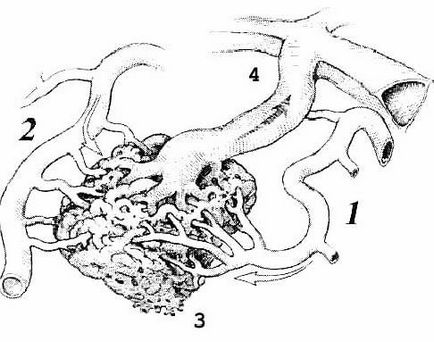

Minden arteriovenosus rendellenességek (AVM) egy tipikus szerkezete:

1.2 - kapott artéria (terminál tranzit és típusa)

3 - a kusza módosított hajók (kernel)

4 - ürítési Bécs